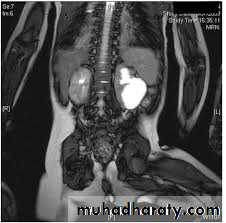

Autosomal dominant (adult) polycystic kidney disease (ADPKD)

ADPKD is an autosomal dominant inherited disorder leading to the development of multiple expanding renal parenchymal cysts.The kidneys reach an enormous size due to multiple fluid-filled cysts and can easily be palpated on abdominal examination. Expansion of the cysts results in ischemic atrophy of the surrounding renal parenchyma and obstruction of normal renal tubules.

End-stage renal failure is inevitable and occurs around the age of 50 years.